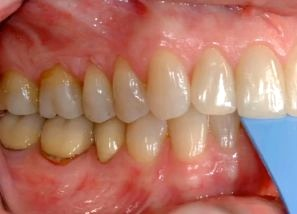

Another way to treat these patients is to mount the models on an articulator in centric relation using a facebow and CR bite records. Let’s say you were planning or restoring the upper posteriors and you wanted to restore them in CR. The models could be equilibrated into CR (mainly at the expense of the upper posteriors, as compared with the lower posteriors). Once the models have been equilibrated, the upper posterior teeth can be diagnostically waxed. Back in the mouth, we now prepare the upper posterior teeth and equilibrate the anterior teeth.

Once the anterior teeth are equilibrated into CR, go back and check the interocclusal distance on the posterior preps to make sure you still have enough occlusal reduction. Then take the final impression and make the provisionals. Because the teeth were waxed on the models in CR, a matrix taken from the wax-up can be used to fabricate the provisionals. The provisionals will then fit into the new CR occlusal scheme.